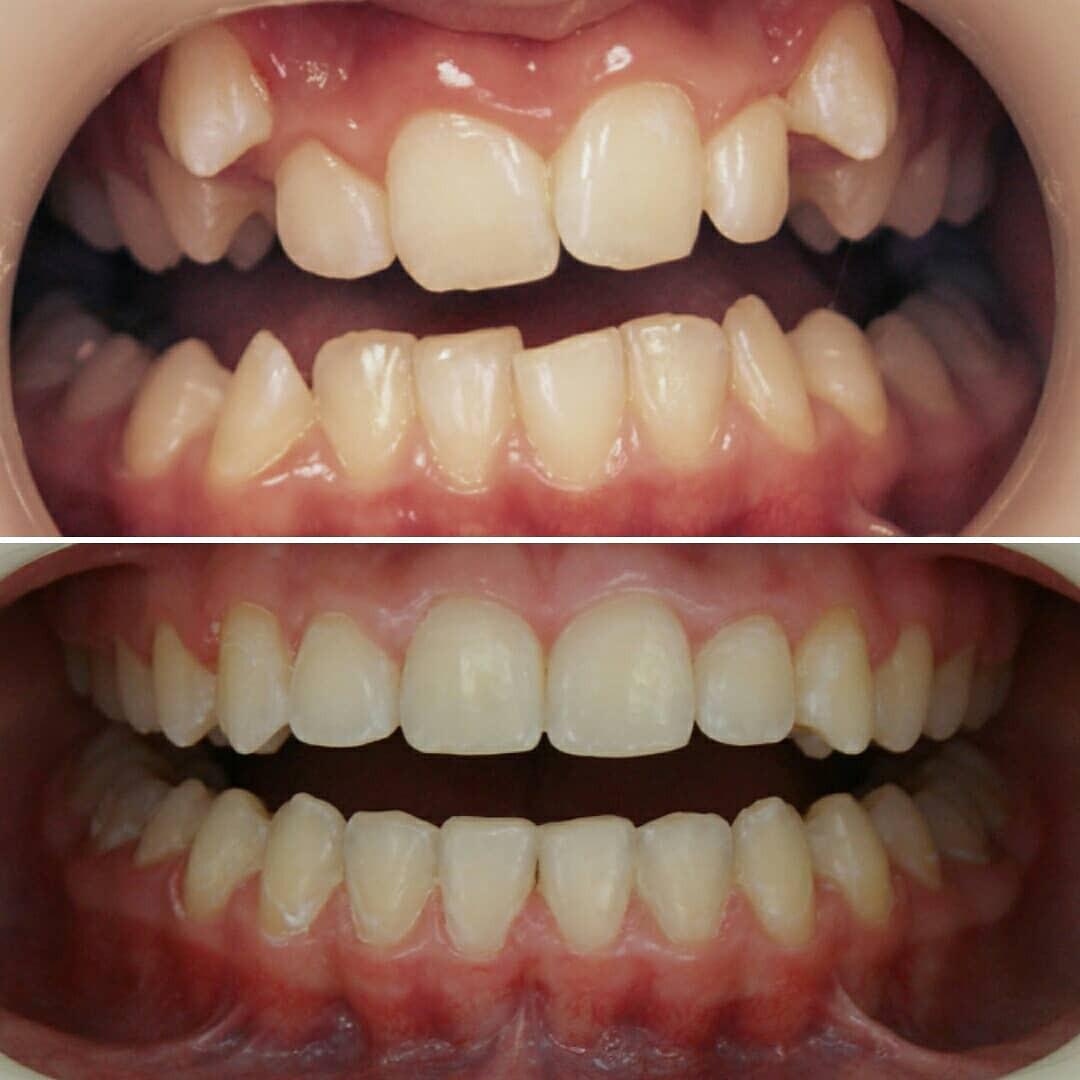

✔Глубокий прикус, дистальный прикус с пространством (щелью) между верхними и нижними резцами, скученное положение зубов, заблокированное нёбное положение верхнего левого зуба ✔Лечение на металлической самолигирующей системе Damon

✔Пациент, 12,5 лет на момент старта ✔Общий срок лечения 18 месяцев ✔Брекеты Damon Q ✔Дистальный, перекрестный, глубокий прикус, смещение нижней челюсти, несоответствие средних линий и сужение зубных рядов, скученность зубов, недостаток места для верхних клыков